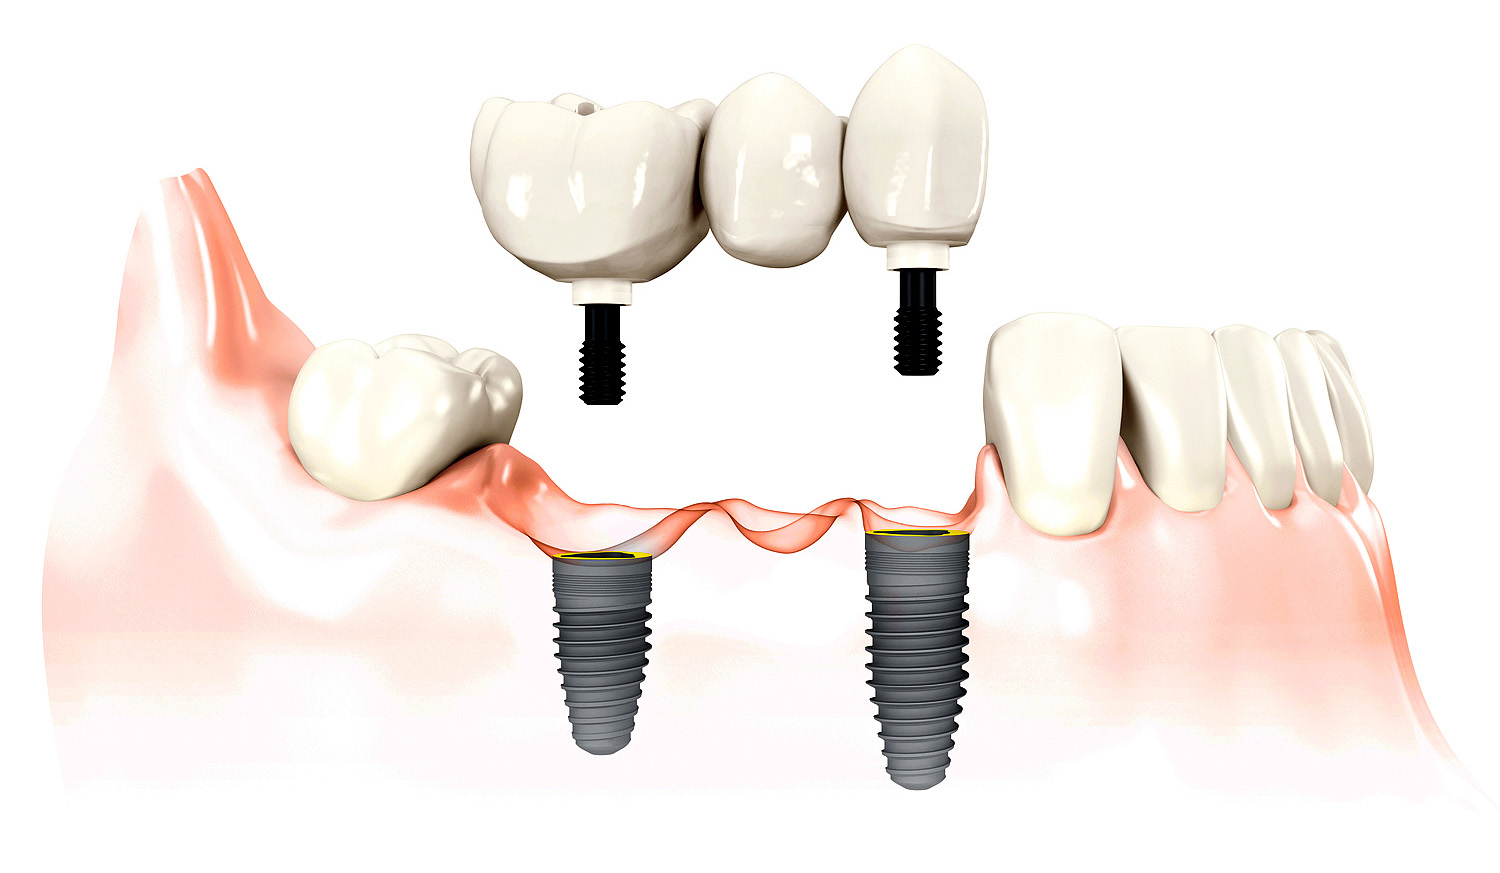

Nelikus nė mažiausių dantų likučių ir atsisakius dantų implantų, tenka gaminti dantų tiltą – dirbtinį dantuką plius du šoninius vainikėlius dantuko tvirtinimui ant nušlifuotų kaimyninių savų dantų.

Jei šoniniai dantys yra sveiki, kam gali būti patrauklus sprendimas juos šlifuoti ir paversti nevisaverčiais? – retoriškai klausia daktaras. – O šlifuoti būtina, kad suvienodinti apvilktų dantų aukštį su dirbtinio ir kitų savų dantų aukščiu. Paskaičiavus, ką „pasiima“ nors vieno dantuko protezavimas be jokio danties likučio ir be implanto, – daugelis pacientų susimąsto iš naujo, ar iš tikrųjų dantis „geriau rauti, nei taisyti“. Jei taisyti neįmanoma, – ženkliai geriau implantuoti, nei protezuoti be implanto. Jei sugydyti dar įmanoma, – visais atvejais geriau danties likutį gydyti ir išsaugoti palankesniam protezavimui.

Profesionaliai sugydytus ir išsaugotus danties likučius arba jo šaknis yra ženkliai paprasčiau ir pigiau apvilkti danties vainikėliu, nei rauti ir implantuoti arba protezuoti aukščiau aprašytu būdu. Jeigu danties kiekio likę per mažai užmauti sandariai karūnėlę, – naudojami kiti įvairūs būdai tą trūkstamą danties kiekį padidinti, pvz., įklotai, užklotai ir pan. Tuomet nereikės nei šlifuoti sveikų šoninių dantų, nei chirurginės implantavimo intervencijos (kainuojančios dažnai daugiau, nei danties ar jo šaknų kanalų gydymas), o žandikaulio kaulas, veikiamas natūralios danties šaknies stimuliuojamo kramtymo krūvio, bus saugomas nuo sunykimo.

Danties implantų privalumas – nereikia šlifuoti kaimyninių dantų ir saugo žandikaulio kaulą nuo sunykimo, nes tęsia visas danties šaknies funkcijas